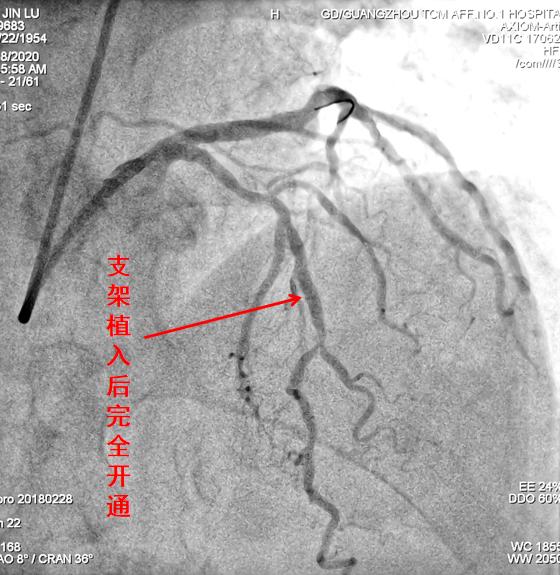

关键还得治疗!医生迅速插入血栓抽吸导管到这条被血栓阻塞的血管分支,抽出血栓,让那些“半死不活”的心肌有了血供,患者的监测指标马上就有了改善。但造影复查发现血管局部仍然存在明显的斑块和狭窄,医生又当机立断为黄伯植入了金属支架,再次造影显示血管已经完全开通,这又为防止短期内再次缺血提供了保障,治疗取得了圆满成功。

治疗后造影复查对比一目了然